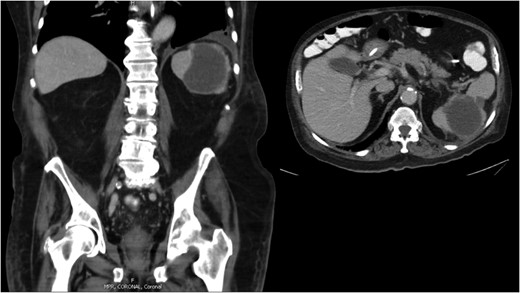

A 75-year-old male presented to clinic with a decline in mental status following 6 weeks of progressive weakness. His past medical history included hypertension, coronary artery disease, stable chronic lymphoid leukemia (CLL) and newly diagnosed congestive heart failure (CHF) with moderate aortic valve insufficiency seen on outpatient echocardiogram 3 weeks earlier. Vital signs were within normal limits, and physical exam revealed a non-focal neurologic examination, diastolic heart murmur and diffuse mild abdominal pain. Admission laboratories were notable for WBC of 18 500/mm3 (slightly increased above CLL baseline), with neutrophil predominance. Brain MRI (Fig. 1) and trans-esophageal echocardiography revealed multiple bilateral areas of restricted diffusion consistent with ischemic stroke, as well as a 2.2 cm aortic valve vegetation with severe aortic regurgitation, but no intra-cardiac abscess. Blood cultures confirmed Enterococcus faecalis endocarditis. Abdominal CT scan (Fig. 2) revealed an 8.1 cm splenic lesion consistent with splenic abscess.

Abdominal CT scan demonstrating an 8.1 cm splenic lesion consistent with splenic abscess.